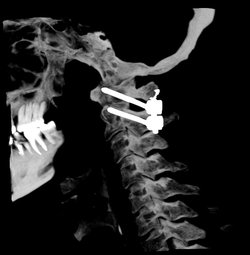

Сюжет ГТРК Томск о методике хирургического лечения пациентов с повреждением верхнешейного отдела позвоночника

«Больница скорой медицинской помощи» - единственное учреждение в Томской области, имеющее операционное техническое оснащение и необходимый современный хирургический инструментарий для выполнения операций пациентам с повреждением верхнешейного отдела позвоночника, что позволяет оперативно осуществлять хирургическое вмешательство в экстренных случаях. Смотрите об этом в сюжете журналистов "Вести-Томск".

Нейрохирурги «Больницы скорой медицинской помощи» освоили методику хирургического лечения пациентов с повреждением верхнешейного отдела позвоночника

Данная хирургическая методика применяется при травматическом повреждении краниовертебрального перехода – границы между основанием черепа и верхнешейным отделом позвоночника, опухолевом поражении, болезни Бехтерева и других патологиях.